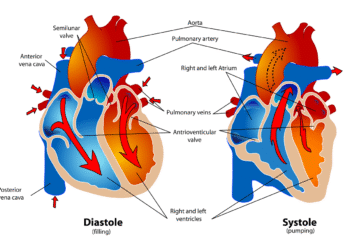

전세계 2천만명의 사람들이 해마다 심혈관질환으로 인해 목숨을 잃는다. 협심증, 심근경색 등의심장질환과 뇌졸중, 뇌출혈 등의 뇌혈관질환으로 대표되는 심혈관질환은 세계 1위의 사망원인이다....

심혈관질환 예방하려면 HDL 높여 ‘콜레스테롤 디톡스’ 해야

심혈관질환 예방을 위해서는 혈관 속 콜레스테롤을 제거하는 디톡스가 필요하다. 12만 킬로미터에 달하는 혈관은 온몸의 세포와 조직에 반드시 필요한 산소와 영양을...